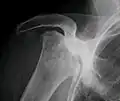

Front X-ray of right knee of an adolescent (epiphyseal plates are open): arrows point to avascular necrosis and developing osteochondritis dissecans in the outer medial condyle of femur

X-ray images of avascular necrosis in the early stages usually appear normal. In later stages it appears relatively more radio-opaque due to the nearby living bone becoming resorbed secondary to reactive hyperemia.[2] The necrotic bone itself does not show increased radiographic opacity, as dead bone cannot undergo bone resorption which is carried out by living osteoclasts.[2] Late radiographic signs also include a radiolucency area following the collapse of subchondral bone (crescent sign) and ringed regions of radiodensity resulting from saponification and calcification of marrow fat following medullary infarcts.